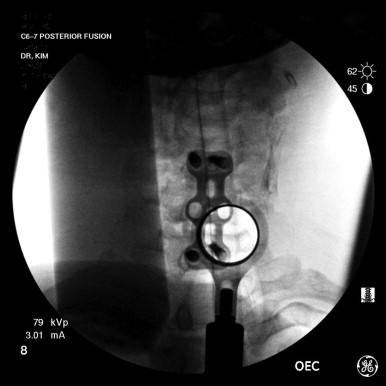

With the minimally invasive approach to PCMF, a spinal needle is inserted approximately 1 to 2 cm off midline at the pertinent level. The target, the junction of the medial facet joint and two laminae, should then be confirmed with intraoperative fluoroscopy. A 12- to 14-mm stablike incision is made over the needle puncture site and is followed by removal of the spinal needle and insertion of a guidewire or a small dilator. The dilator is preferred over the guidewire to avoid penetration of the ligamentum flavum and creation of an inadvertent durotomy.

The dilator should be advanced and docked on the corresponding lateral mass. This can be confirmed by intraoperative fluoroscopy. Gentle soft-tissue dissection is carried out with subsequent dilators until the appropriate sized tubular retractor can be inserted. The location should again be confirmed by intraoperative fluoroscopy ( Fig. 20-3 ). The operative microscope is then brought over the surgical field to allow for direct visualization of the corresponding laminae and facet joint. The subsequent steps, whether done via a minimally invasive approach or by open PCMF, are identical and are described below.